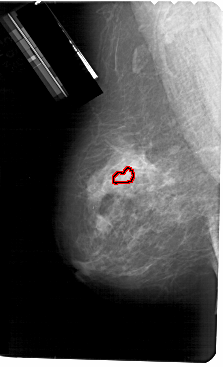

FILE: A_1631_1.LEFT_MLO.OVERLAY

TOTAL_ABNORMALITIES 1

ABNORMALITY 1

LESION_TYPE CALCIFICATION TYPE PLEOMORPHIC DISTRIBUTION CLUSTERED

ASSESSMENT 4

SUBTLETY 2

PATHOLOGY BENIGN

TOTAL_OUTLINES 1

BOUNDARY